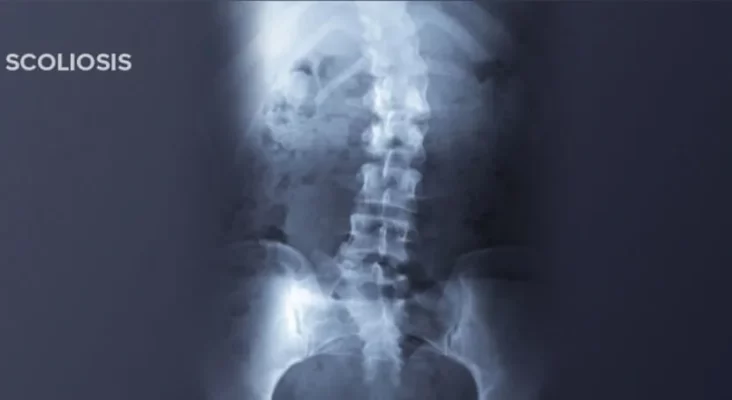

脊柱側弯症のレッドフラッグの見分け方:ステップバイステップガイド

I. Introduction Scoliosis is a common but potentially overlooked health problem, especially in adolescence and [...]